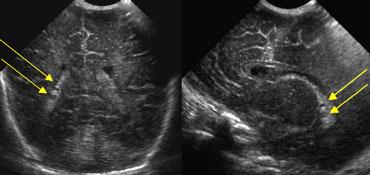

TRÁI: Mặt cắt đứng ngang, mũi tên xanh lá chỉ xuất huyết độ 3. PHẢI: Mặt cắt đứng dọc, mũi tên vàng chỉ nhồi máu tĩnh mạch.

Xuất huyết nội sọ độ 3

Hình bên trái là xuất huyết nội sọ độ 3 lấp đầy não thất bên trái.

Cũng lưu ý vùng tăng âm hình nêm ở phía trên-bên của não thất.

Đây là hình ảnh của một ổ nhồi máu tĩnh mạch nhỏ.

Cùng bệnh nhân như trên.

Hai tuần sau, ổ nhồi máu tĩnh mạch đã tiến triển thành vùng giảm âm với sự hình thành nang.